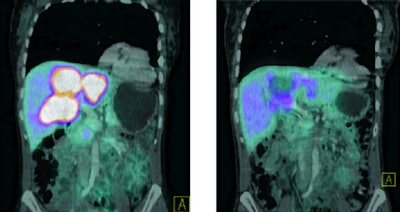

| Response to Bi-123 DOTANOC treatment observed in patients with tumors resistant to previous therapy with yttrium-90 and lutetium-177. Image above shows shrinkage of liver lesions and bone metastases after therapy with 11 GBq of Bi-123 DOTANOC. Image below shows response of multiple liver lesions after therapy with 14 GBq of Bi-123 DOTANOC. Images courtesy of SNM. |

Most importantly, the researchers observed shrinkage of the primary tumors, as well as liver and bone metastases.